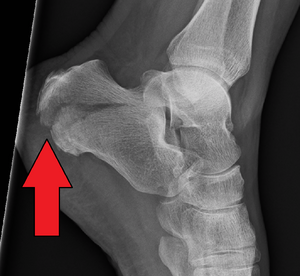

The most common symptom is pain over the heel area, especially when the heel is palpated or squeezed. Patients usually have a history of recent trauma to the area or fall from a height. Other symptoms include: inability to bear weight over the involved foot, limited mobility of the foot, and limping. Upon inspection, the examiner may notice swelling, redness, and hematomas. A hematoma extending to the sole of the foot is called "Mondor Sign", and is pathognomonic for calcaneal fracture.[3][4] The heel may also become widened with associated edema due to displacement of lateral calcaneal border. Soft tissue involvement should be evaluated because of the association with serious complications (see below).[5][6]